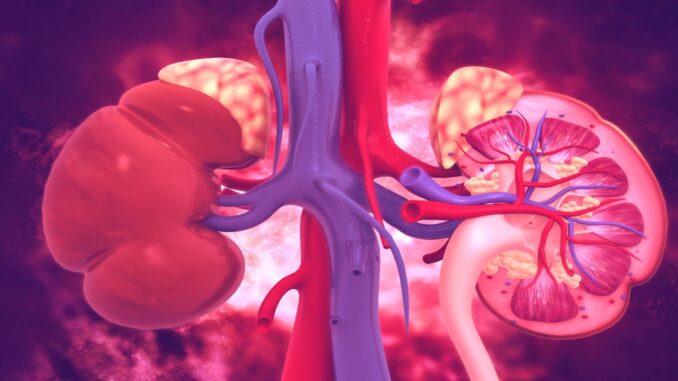

Rakovina ledvin: Příznaky, příčiny a léčba. Vše, co potřebujete vědět o této zákeřné nemoci

Neexistuje žádná běžná příčina rakoviny ledvin, i když dědičné onemocnění, vystavení určitým látkám, záření, závislost hrají důležitou roli.

Nádor ledvin se vyvíjí, když se jeho buňky degenerují na patologické a rostou, čímž narušují funkci tkáně. Pokud je průběh onemocnění benigní, existuje šance na úplné odstranění nádoru.

Maligní nádor vyžaduje dlouhodobou léčbu a prognóza bude záviset na typu nádoru, stádiu vývoje a přítomnosti metastáz. Existují dva typy nádorů ledvin: benigní a maligní.